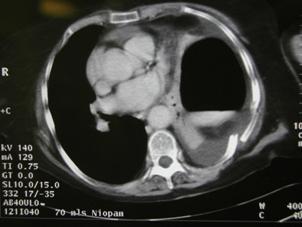

Aspect radiologic Imagine CT

Imagine

CT Imagine CT